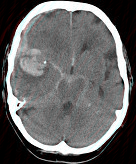

- 单项选择题女,79岁, 突发神志不清,请结合影像图像判断其最可能的诊断 ( )

A、脑转移瘤出血

B、脑脓肿

C、脑梗死

D、右大脑中动脉破裂出血

E、脑膜炎